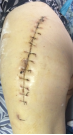

病例1 患者周某,女性,73歲,右髖關(guān)節(jié)置換術(shù)后15年,出現(xiàn)假體松動(dòng)并感染,在我院住院治療,關(guān)節(jié)假體感染翻修被稱為“關(guān)節(jié)外科醫(yī)生的終極挑戰(zhàn)”,老年骨科專家團(tuán)隊(duì)不畏艱險(xiǎn),應(yīng)用301醫(yī)院假體周圍感染翻修的先進(jìn)經(jīng)驗(yàn),采取二期翻修方案,整個(gè)治療分兩步進(jìn)行,第一次手術(shù)取出假體,清除感染,置入帶抗生素的骨水泥占位器,再進(jìn)行6個(gè)月左右的抗感染治療;感染控制后,再進(jìn)行第二次手術(shù),植入翻修人工關(guān)節(jié),并確保感染完全控制;患者經(jīng)過半年時(shí)間的治療,感染得到徹底控制,順利進(jìn)行了髖關(guān)節(jié)翻修手術(shù)。

術(shù)前資料

第一次手術(shù)后

第2次手術(shù)后